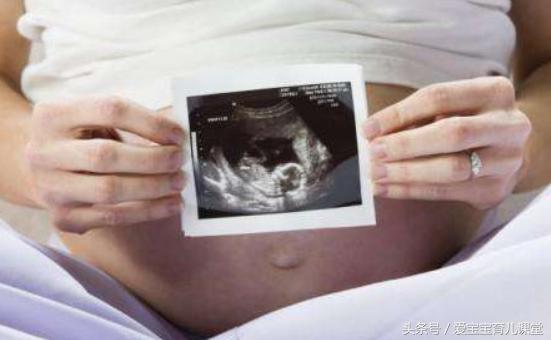

周末,冯女士在老公的陪伴下,去医院做最后一次产检,顺便问问生产前还有什么需要特别准备的,可是就在做完B超检查后,医生的话却让冯女士的心一下子悬了起来。

原来,B超上显示,冯女士腹中胎儿的勃颈处,有明显的压痕,根据医生的判断应该是脐带绕颈了,而且至少4周以上,有窒息的危险,胎心显得也很不稳定,要求冯女士立刻住院,准备进行剖腹产。